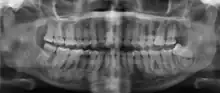

| Florid osseous dysplasia of the mandible | |

Cemento-osseous dysplasia (COD) is a benign condition of the jaws that may arise from the fibroblasts of the periodontal ligaments. It is most common in African-American females. The three types are periapical cemental dysplasia (common in those of African descent), focal cemento-osseous dysplasia (Caucasians), and florid cemento-osseous dysplasia (African descent). Periapical occurs most commonly in the mandibular anterior teeth while focal appears predominantly in the mandibular posterior teeth and florid in both maxilla and mandible in multiple quadrants.

Diagnosis is important so that the treating doctor does not confuse it for another periapical disease such as rarefying osteitis or condensing osteitis. Incorrect diagnosis could lead to unnecessary root canal treatments. It can be diagnosed by radiographic appearance. Confirming the tooth is vital, as is noting the demographic (African American females).[1][2][3]